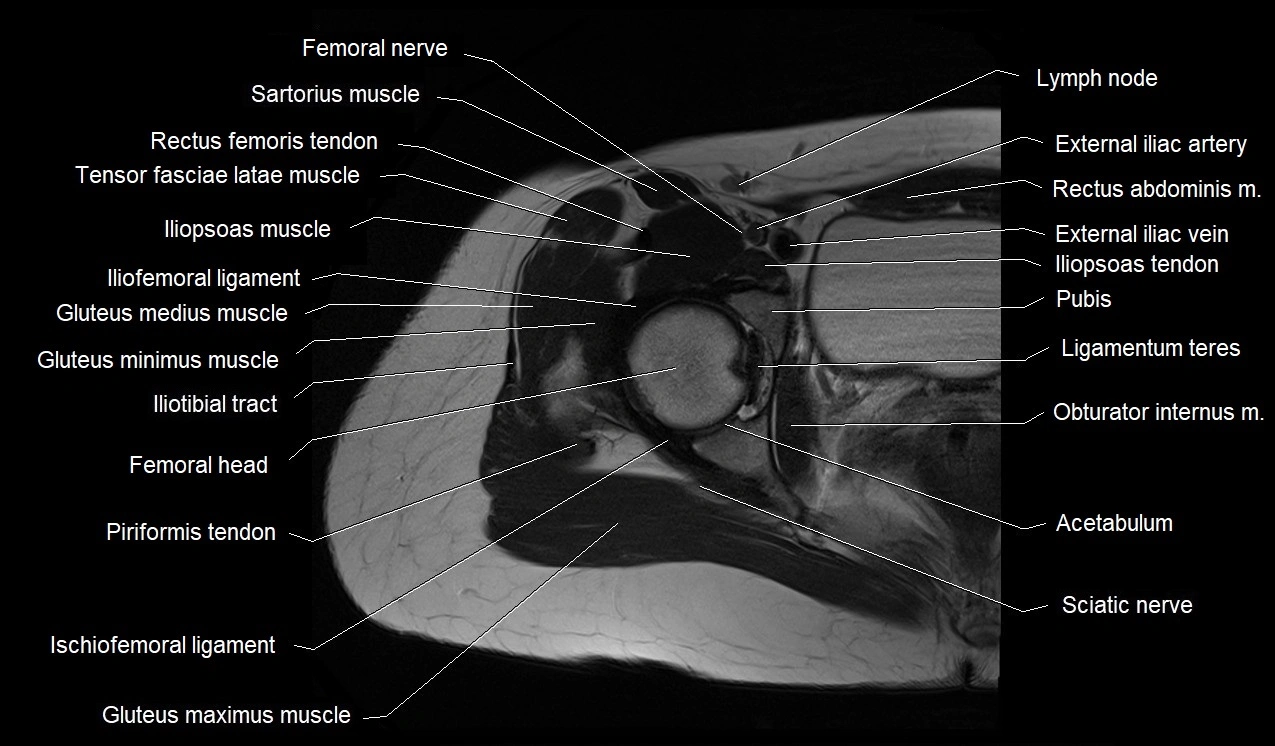

- Femoral nerve

- Sartorius muscle

- Rectus femoris tendon (Proximal tendon of rectus femoris)

- Tensor fasciae latae muscle

- Iliopsoas muscle

- Iliofemoral ligament

- Gluteus medius muscle

- Gluteus minimus muscle

- Iliotibial tract

- Head of femur

- Ischiofemoral ligament

- Ligamentum teres (ligament of the head of femur)

- Acetabulum

- External iliac artery

- External iliac vein

- Gluteus maximus muscle

- Obturator internus muscle

- Sacral plexus

- Superior gemellus muscle